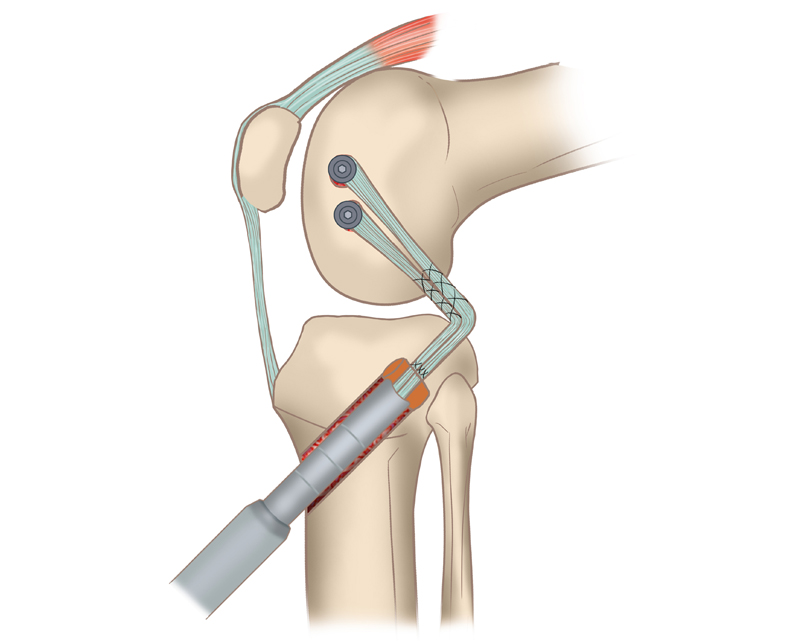

It is a minimally invasive surgery where your Torned Posterior cruciate ligament in the knee is replaced by your own tissue graft through tiny holes made on the knee using tiny instruments

We are going to replace your tornedPCL with the new tendon graft taken from your own leg on the same side of the injured knee or opposite side.

This procedure is done under anesthesia always by making small incisions on your knee joint and using tiny instruments and camera guidance.

The surgery is performed through small incisions in the knee using an arthroscope. The torn ligament is removed, and the synthetic ligament is attached to the bones of the knee using screws or other fixation devices.